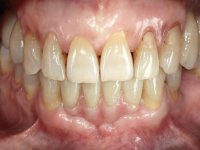

Após estudo imagiológico foi planificada a colocação de dois implantes de 3.3 mm de diâmetro e 10 mm de comprimento. No dia da cirurgia foram extraídos os dentes 42 e 32 e removido o implante. Os implantes foram colocados na zona dos alvéolos tendo o cuidado de lingualizar um pouco o seu posicionamento. Foi feita uma impressão pela técnica de moldeira aberta com o retalho aberto para a confeção da ponte provisória imediata. Enquanto a impressão foi para o laboratório, foram colocados parafusos de cicatrização altos e feita a sutura da ferida cirúrgica. A paciente esperou 2 horas na sala de espera enquanto no laboratório era confecionada a ponte provisória. A ponte provisória imediata aparafusada foi colocada e o seu assentamento controlado imagiologicmente. Passados 3 meses foi realizada a impressão definitiva com uma técnica de moldeira aberta. Nessa consulta aproveitamos para polir a ponte provisória com taças de borracha para que os tecidos moles pudessem maturar em melhores condições. Foi feita a recolha de informação para caracterizar da melhor forma a estrutura monolítica em Zr. Foram utilizadas guias de cor para a cerâmica de tonalidade coronária e gengival. No laboratório foi confecionada uma ponte em Zr. aparafusada que foi cuidadosamente caracterizada. Após aprovação pela paciente foi colocada definitivamente em boca. O aperto foi feito com uma chave dinâmica com 35 N de torque. Os orifícios foram tapados com teflon e obturados com resina composta.